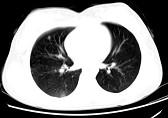

问题 女,24岁,HCG阳性,咯血2天,行胸部CT扫描如图,其最可能的诊断为 ( )

选项 A.转移性绒癌 B.肺部感染 C.肺结核 D.肺血管瘤 E.肺淋巴管肌瘤

答案 A